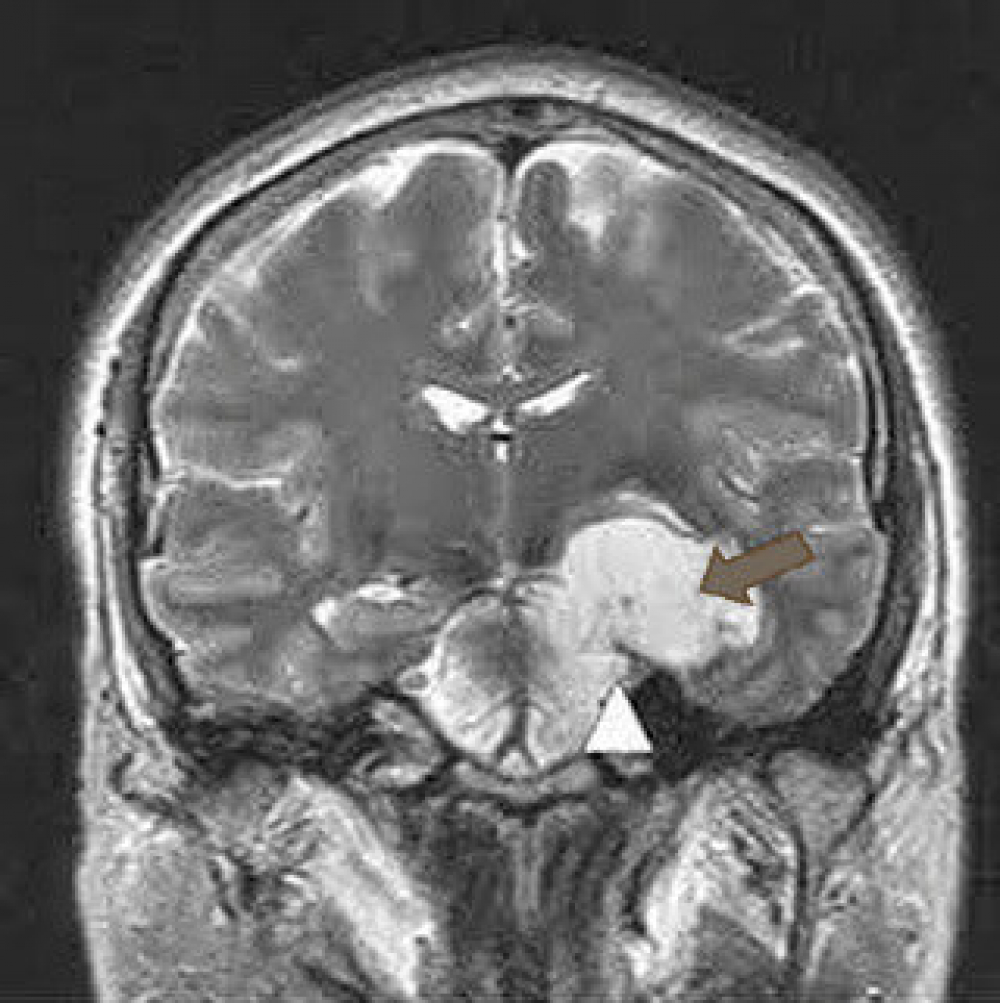

Paciente de 29 años, que acude a consulta tras IQ (hace 6 años) de quiste Epidermoide del ángulo pontocerebeloso. Abordaje temporo parietal derecho.